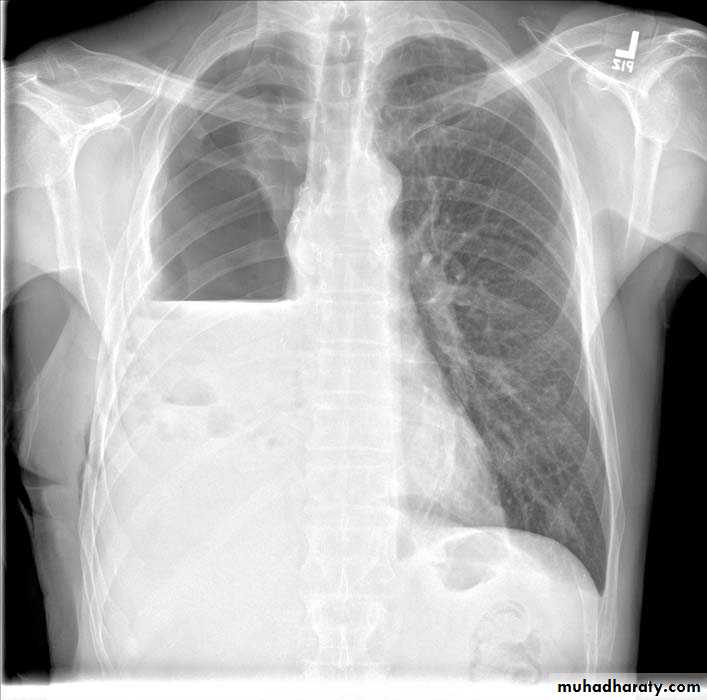

Pleural effusion

50.pleural effusion

51.pleural effusion .